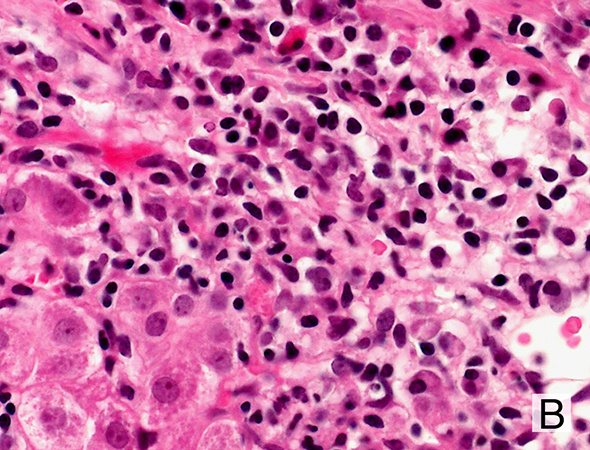

Histologie der klassischen AIH

Schwere Portalentzündung und kontinuierliche Interphasen-Hepatitis (Piecemealnekrosen).

Interphasen-Hepatitis: Beachte Reichtum an Plasmazellen.

Interphasen-Hepatitis mit Rosettenbildung als Ausdruck der regenerativen Aktivität.

Die Histologie hat ein grosses Gewicht in der Diagnostik. Interphasen-Hepatitis, d.h. dichte, vorwiegend lympho-plasmozelluläre portale und periportale/periseptale Infiltrate mit oft reichlich Plasmazellen und Mottenfrassnekrosen sind wegleitend.